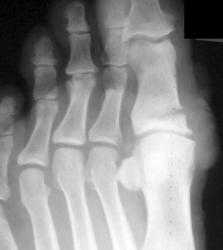

Вот еще, как по заказу сегодня случай попался

Изображение

Все наоборот вставилось Недоволен первый снимок - через 1.5 мес после травмы, второй - исходный.